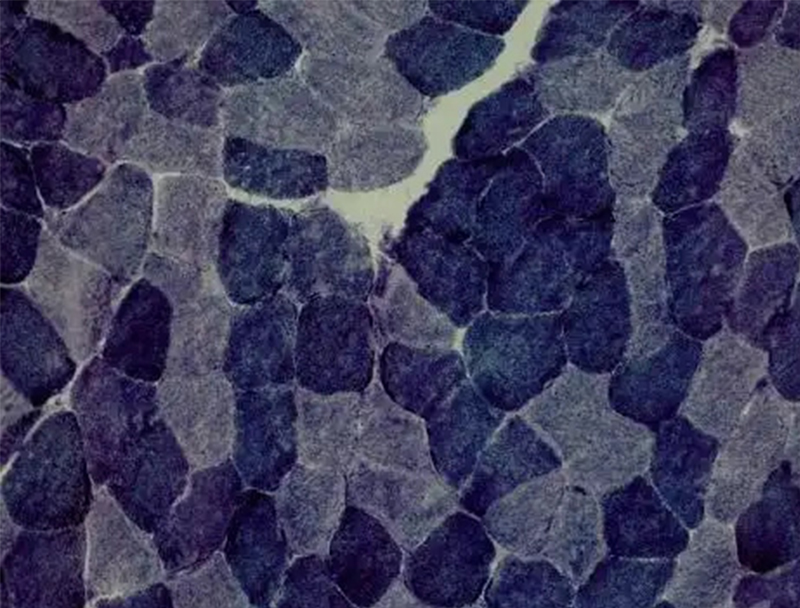

以下是關于 ATP 酶染色的相關介紹:基本原理ATP 酶是一種水解酶,可催化 ATP 分解產生能量。在 ATP 酶染色中,常用的是鈣鈷法,其原理是 ATP 酶水解 ATP 為 ADP 和磷酸,磷酸與鈣離子在酶活性部位結合形成無色的磷酸···